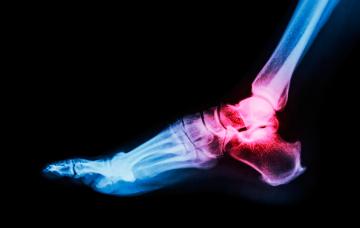

La gota se caracteriza por episodios repetidos de dolor articular e inflamación como consecuencia del depósito de cristales de ácido úrico en las articulaciones.

Fases y síntomas de la gota

Podríamos diferenciar tres fases en la aparición de la gota: desde la asintomática, al ataque agudo finalizando en la cronicidad. Conoce sus complicaciones.